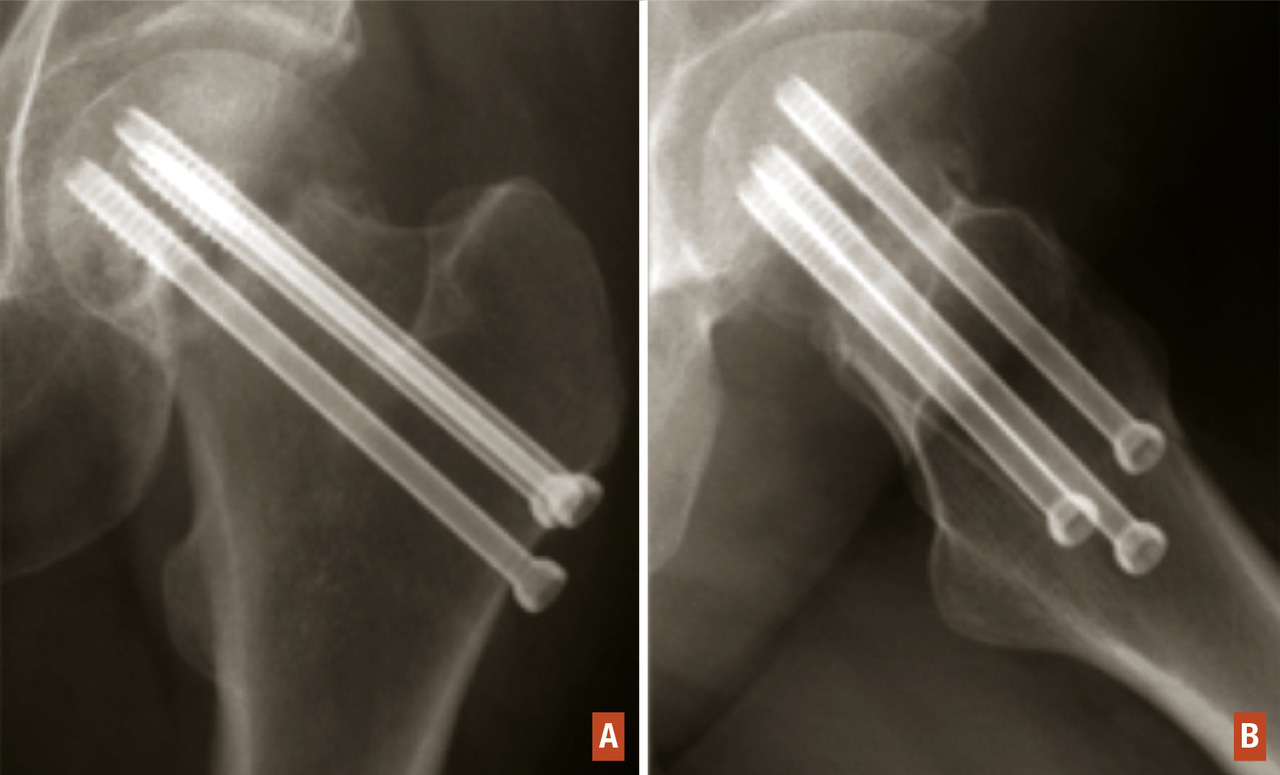

En cas de fracture cervicale vraie, Garden I ou II, où le risque de nécrose est modéré, il est indiqué de réaliser une ostéosynthèse soit par un vissage du col (fig. 13) qui peut être réalisé pratiquement de façon percutanée, soit par la mise en place d’une vis-plaque, plus stable mais nécessitant un abord un peu plus étendu. Toutefois, si le déplacement sur le profil est important ou si la qualité osseuse est médiocre, un traitement par arthroplastie peut être proposé. Enfin, si un traitement fonctionnel est choisi pour des raisons d’ordre général, le risque de déplacement secondaire est important, de 14 à 66 % en fonction des études.